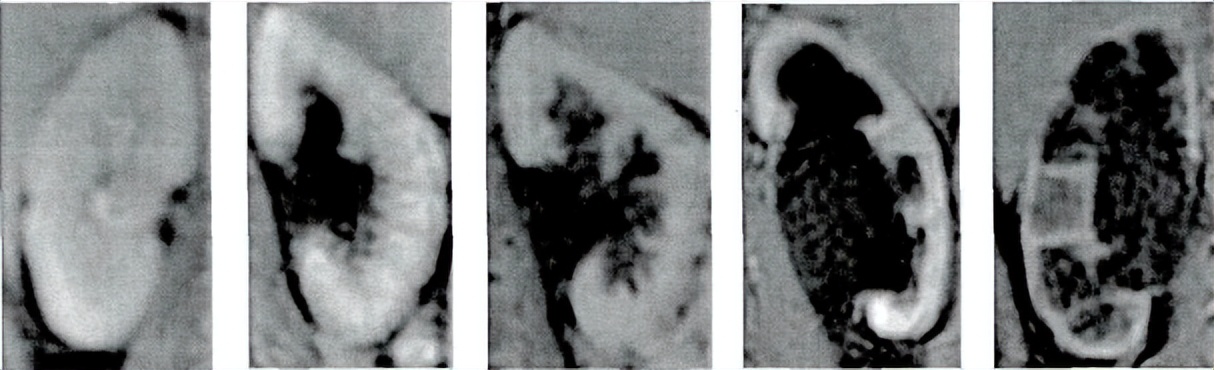

A b c d e

图像选取于研宂人群中增强后动态T1扫描。

a:6月男孩

B:6岁女孩

c:4岁女孩

d:7岁男孩

e:7岁女孩。